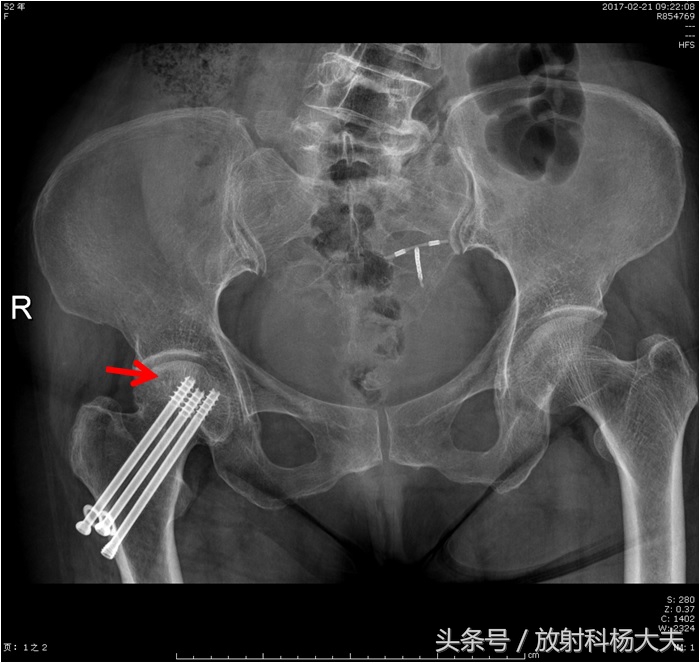

红箭为右侧股骨头坏死。可见植入体内的金属钉

保守治疗,约一年后复查,这次又拍了X光片。